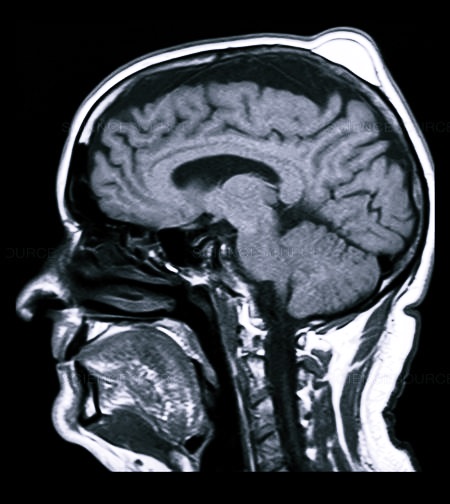

На голове проводится и УЗИ исследование, помогающее определить видоизменения в тканях и костных структурах, иногда МРТ, в виде дополнительной меры диагностики.